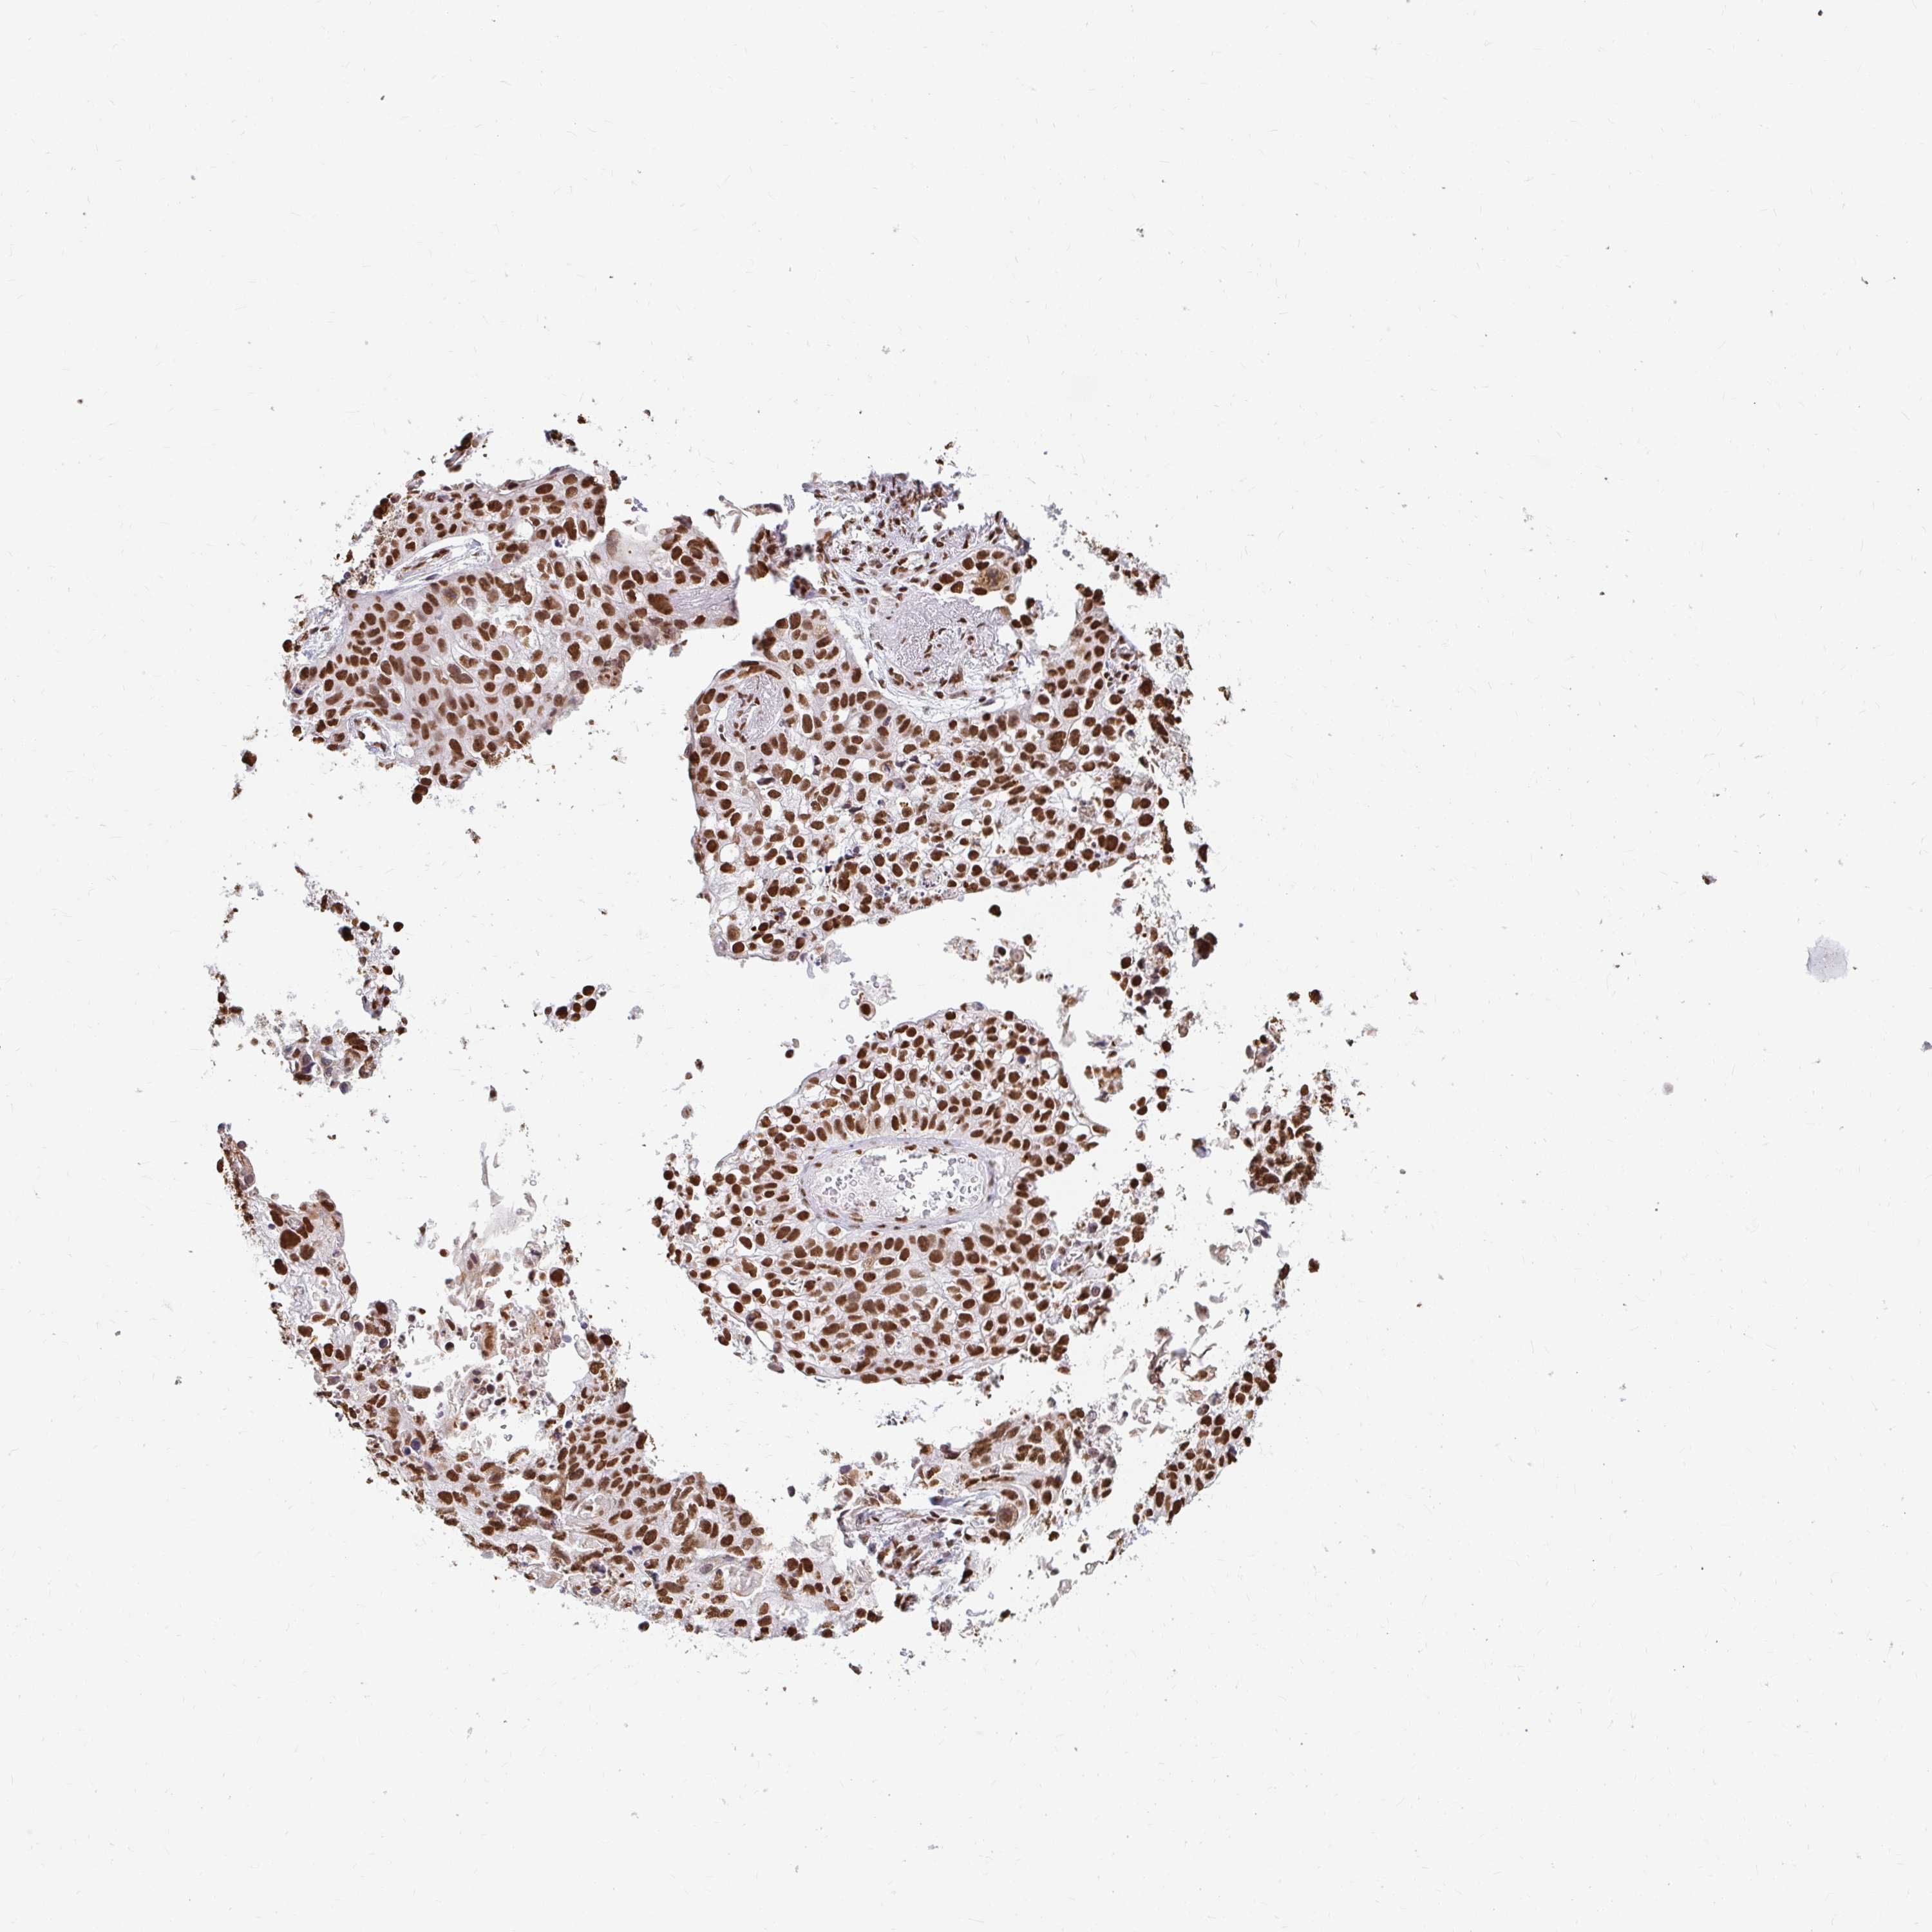

LUNG SQUAMOUS CELL CARCINOMA (TCGA) - Interactive survival scatter ploti

The Survival Scatter plot shows the clinical status (i.e. dead or alive) for all individuals in the patient cohort, based on the same data that underlies the corresponding Kaplan-Meier plots. Patients that are alive at last time for follow-up are shown in blue and patients who have died during the study are shown in red.

The x-axis shows the expression levels (FPKM) of the investigated gene in the tumor tissue at the time of diagnosis. The y-axis shows the follow-up time after diagnosis (years). Both axes are complimented with kernel density curves demonstrating the data density over the axes. The top density plot shows the expression levels (FPKM) distribution among dead (red) and alive patients (blue). The right density plot shows the data density of the survived years of dead patients with high and low expression levels respectively, stratified using the cutoff indicated by the vertical dashed line through the Survival Scatter plot. This cutoff is automatically defined based on the FPKM cutoff that minimizes the p-score. The cutoff can be changed by dragging the vertical line or by entering a cutoff value in the square labeled "Current cut-off".

Under the Survival Scatter plot the p-score landscape (black curve; left axis) is shown together with dead median separation (red curve; right axis). Dead median separation is the difference in median mRNA expression between patients who have died with high and low expression, respectively. It is calculated as follows: median FPKM expression of dead patients with high expression - median FPKM expression of dead patients with low expression. This is intended to aid the user in visually exploring custom cutoffs and the associated p-scores and dead median separation.

Individual patient data is displayed and can be filtered by clicking on one or more of the category buttons on the top of the page. Categories describing expression level and patient information include: high, low, alive, dead, female, male and tumor stages. The scale of the x-axis can be toggled between linear and log-scale by clicking on the "x log" button. Mouse-over function shows TCGA ID, patient information and mRNA expression (FPKM) for each patient.

& Survival analysisi

Kaplan-Meier plots summarize results from analysis of correlation between mRNA expression level and patient survival. Patients were divided based on level of expression into one of the two groups "low" (under cut off) or "high" (over cut off). X-axis shows time for survival (years) and y-axis shows the probability of survival, where 1.0 corresponds to 100 percent.

HNRNPU is not prognostic in Lung Squamous Cell Carcinoma (TCGA)

Best expression cut offi

Based on the FPKM value of each gene, patients were classified into two groups and association between prognosis (survival) and gene expression (FPKM) was examined. The best expression cut-off refers the FPKM value that yields maximal difference with regard to survival between the two groups at the lowest log-rank P-value. Best expression cut-off was selected based on survival analysis .

When clicking on this number, the vertical dashed line indicating cut-off, the interactive survival plot, and the Kaplan-Meier curve will be adjusted to show results based on the best expression cut-off.

: 136.2

P scorei

Log-rank P value for Kaplan-Meier plot showing results from analysis of correlation between mRNA expression level and patient survival.

N/A

Average pTPM 163.2

Number of samples 489